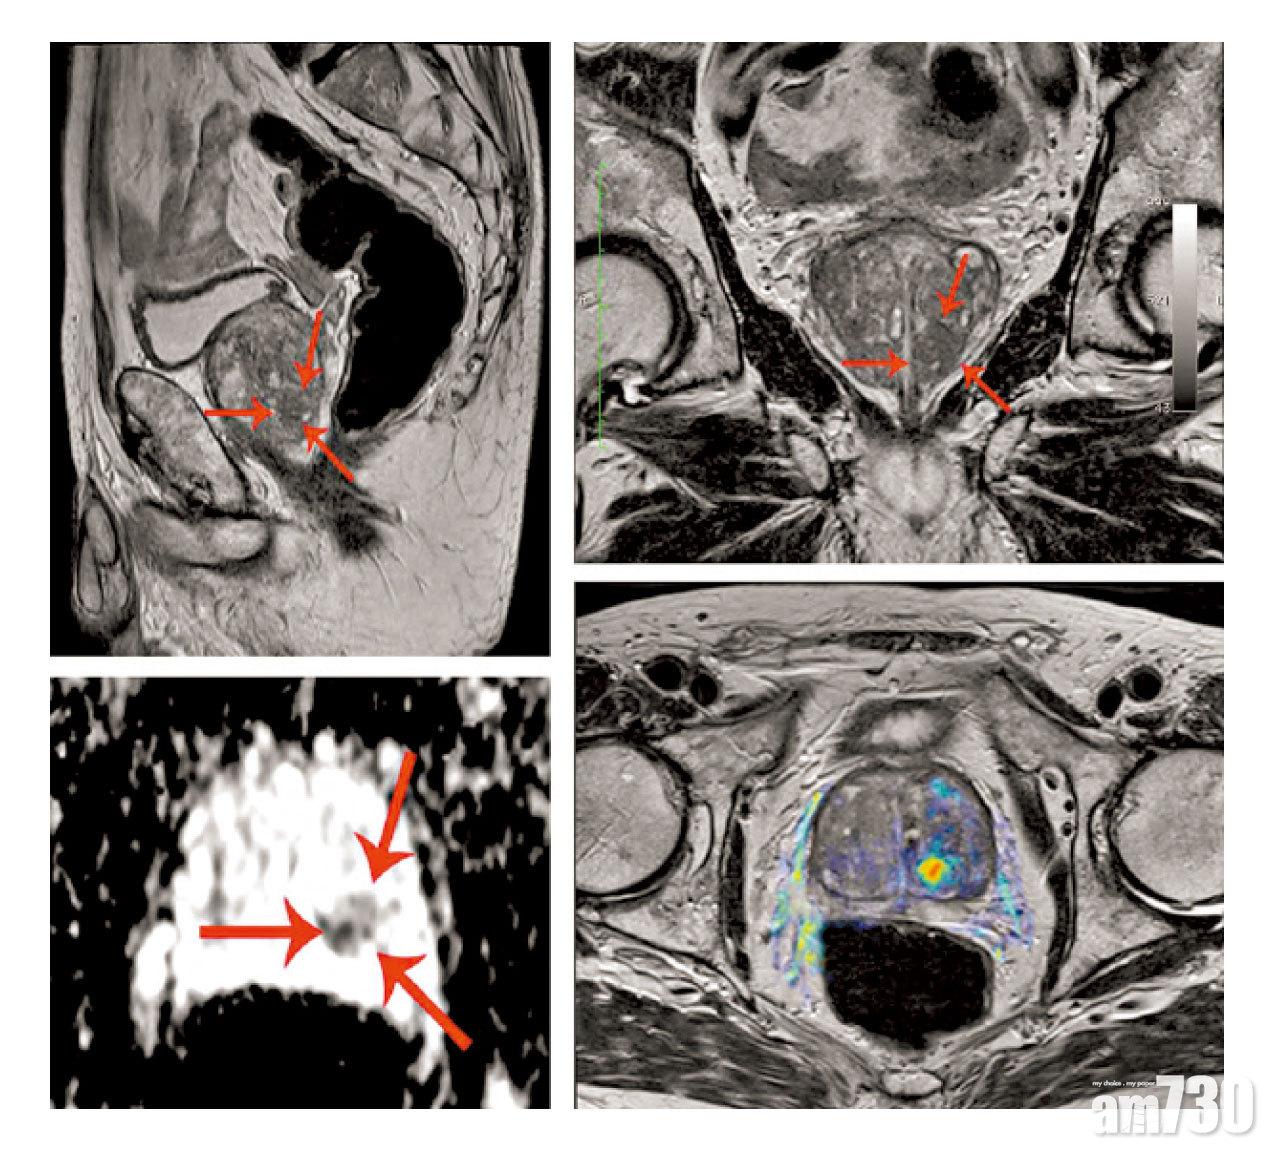

磁力共振檢查可作前列腺癌風險評估,也有助提升抽針準確度。

病人每年都抽針碰運氣當然不理想,幸好現在對PSA超標的處理方法已大幅改進,以磁力共振檢查為主,「檢查時若發現疑似腫瘤的陰影,放射科醫生會將陰影分為1至5分,1至2分代表風險不高,3至4分代表風險頗高,5分代表有相當大可能是前列腺癌。」

而在抽針方面現在亦會採用磁力共振導航抽針,傅錦峰解釋,「做法其實是將磁力共振和超聲波混合使用,以超聲波顯示前列腺的實時影像,由磁力共振導航至檢測出陰影的位置抽針,並非隨機而是有針對性,因此準確度大幅提升,亦減少了『無辜』的位置被抽針,因此風險較低,出血也較少。」